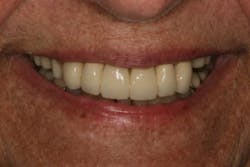

In this case, the diagnostic wax-up of the mounted models gave the technician the new position of the upper incisal edge. The technician then set the maxillary teeth appropriately using models and additional photographs. At the same time, tooth No. 20 was restored, but the lab technician kept the crown and lower partial to predictably create the lower occlusal plane and easily articulate this with the upper immediate denture (figure 18). Note the improved curve of Spee in Figures 19 and 20. Upon completion of the prosthesis, treatment was completed as outlined and the results made the patient feel very comfortable functionally, esthetically, and phonetically.

There was some fine-tuning to the patient's occlusion during the healing period. Nevertheless, the goals of treatment were accomplished very predictably. Figures 21 (horizontal position) and 22 (vertical position) verify both the new vertical and horizontal positions of the upper incisal edge.

Understanding the patient’s masticatory system requires the dentist to gather the correct data through a comprehensive examination. (6) In addition, diagnostic records (mounted models in centric relation and digital photography) can be used to provide predictable results. The overall esthetic outcome, along with improved function, gave the patient a new outlook on life and increased confidence—all within her budget (figures 23–25). The Dawson Academy is a great resource for learning about the masticatory system, functional esthetics, and a predictable treatment-planning protocol.